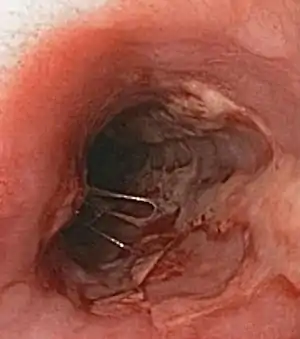

| Herpes esophagitis | Symptoms may include painful swallowing (odynophagia) and difficulty swallowing (dysphagia). It is often associated with impaired immune function (e.g. HIV/AIDS, immunosuppression in solid organ transplants). | ![]() |